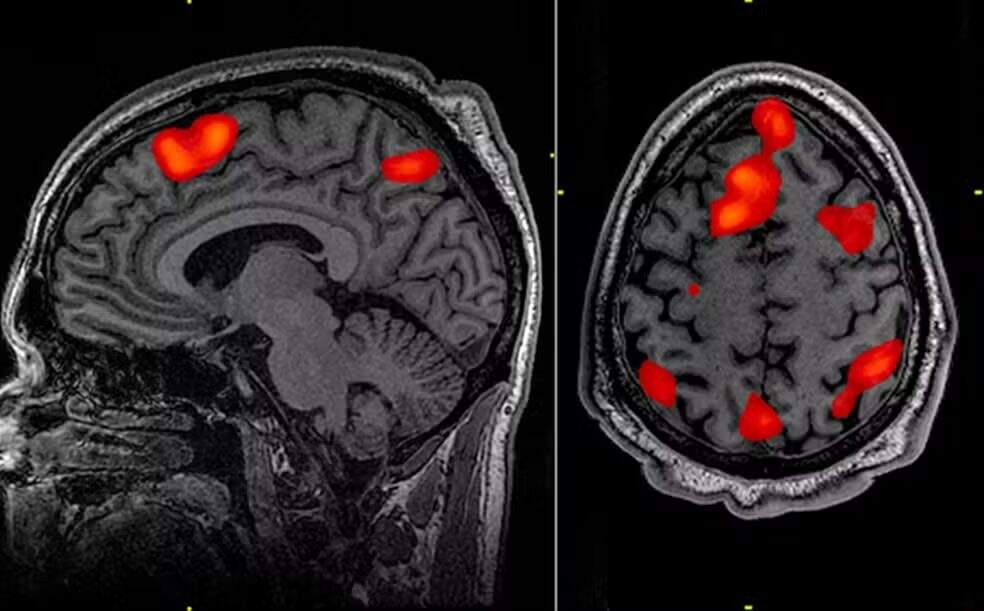

Ele é introduzido profundamente no cérebro, usando imagens de ressonância magnética para orientar um microcateter em duas regiões do cérebro, o núcleo caudado e o putâmen. A neurocirurgia leva entre 12 e 18 horas.

Os dados demonstram que, três anos após a cirurgia, houve, em média, 75% de redução da velocidade de avanço da doença, com base em uma medição que combina a cognição, funções motoras e a capacidade de se autogerenciar no dia a dia. Os dados também demonstram que o tratamento está salvando as células cerebrais.